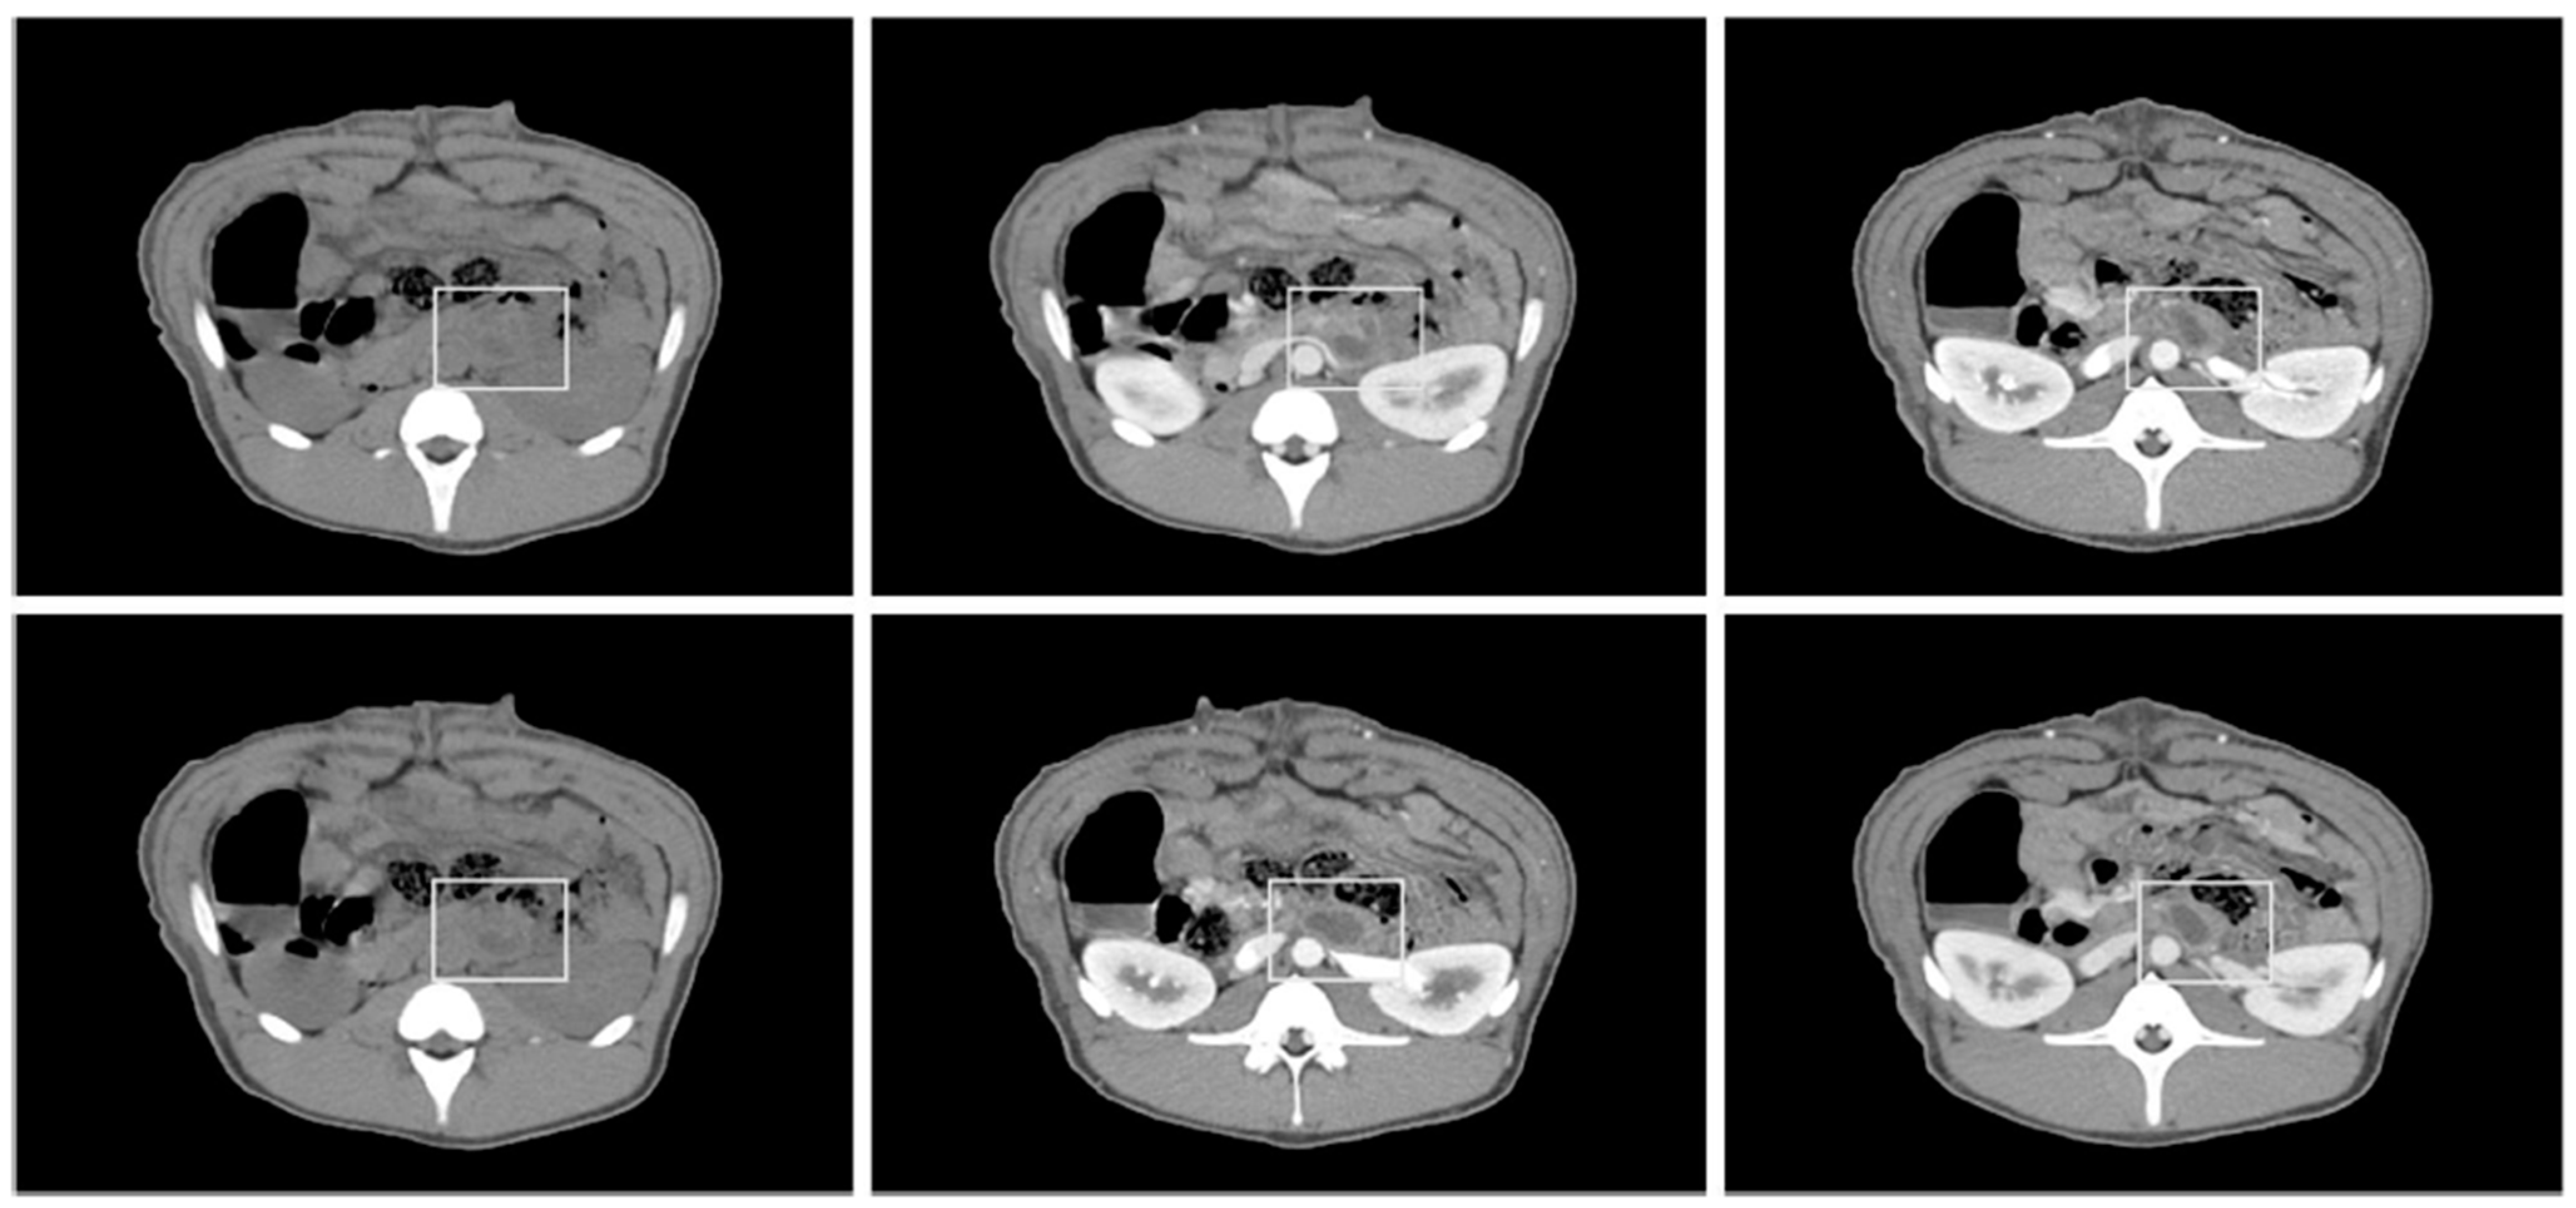

3.3. CT and Necropsy